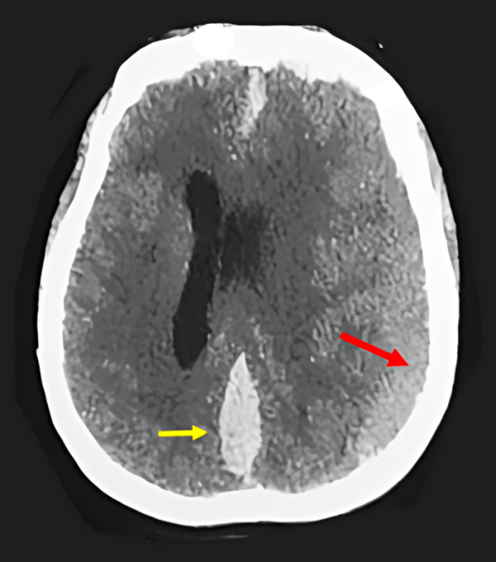

We report a 55-years-old woman presented with consciousness disorder with vomiting for 2 days. Past history revealed a mitral replacement in 2008 and she had beeing using anticoagulant agent (Acenocoumarol). The neurologic examination revealed a disorder of consciousness was 07/15 assessed by the Glasgow Coma Scale (GCS), pupil in myosis, stiff neck. The biological check-up showed a platelet count was 219,000/mm3, and thrombo test was 55% and an International Normalized Ratio of 1.39. CT (computed tomography) scan of the head showed a left subacute subdural hemispheric hematoma compressive with subfalcoral engagement associated with an acute ISDH (Figure 1). Consequently, we proceeded with the surgical evacuation of the left subdural hematoma via two burr-hole fronto-parietal craniotomy then she was transferred to the intensive careunit. The anticoagulant agent was stopped. The patient is still intubated, the sedation was stopped 3 days postoperatively with no sign of awakening. A control CT scan was performed three days after, showing only the acute IHSDH (Figure 2).

Figure 1: CT-scan of the head showed a left subacute HSDH (yellow arrow) compressive with subfalcoral engagement associated with an acute IHSDH (red arrow).